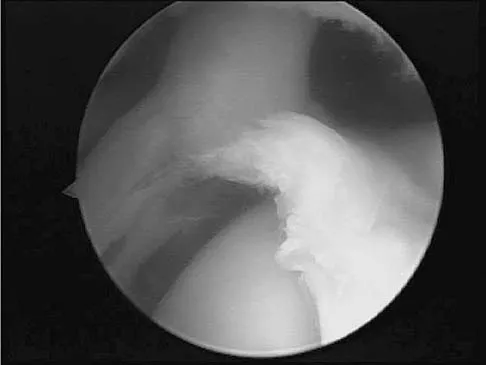

A patient has right shoulder pain. Figure 1a shows a gadolinium-enhanced transverse MRI scan at the level of the coracoid. Figure 1b shows an arthroscopic view of the anterior structures from a posterior portal. These images reveal which of the following findings?

Explanation